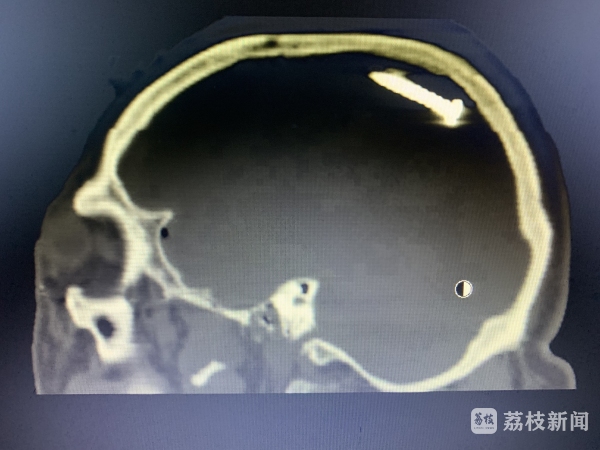

7月10日周六中午,正在家中休息的张勇接到医院电话,120急救车送来一位52岁的脑外伤患者,脑内有钉样异物,一侧瞳孔已经散大。身旁的工友描述,施工时使用射钉枪,不小心水泥钉从额部飞进脑门。结合影像检查及术中所见,可以判断水泥钉是从左前额进入颅内,穿过左脑,撞击后方颅骨后又转向前上方。途中转了个圈,形成长约二十几公分的脑内伤道,割破大脑镰,还搅破了很多小血管,形成小的创伤性动脉瘤,并形成了大量伤道内血肿。“所幸术前备了c臂、瘤夹等,几经周折,花费了10余小时终于顺利清除钢钉、碎骨片及大量血肿,复查CT提示手术效果满意。”张主任说,只要患者顺利度过感染关,预后应该是比较理想的。